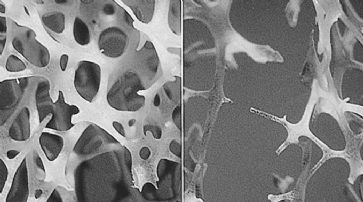

Glasknochenkrankheit: Hoffnung auf neue Therapie

Houston - Eine Entdeckung des Baylor College of Medicine bei Mäusen könnte helfen, Patienten mit Osteogenesis imperfecta (Glasknochenkrankheit) zu behandeln.

Bei mit der Krankheit gezüchteten Tieren wurde die Aktivität eines Proteins nachgewiesen, das die Knochen formt und auch umformen kann. Laut dem Team um Brendan Lee steht die starke Aktivität des Proteins mit Osteogenesis imperfecta in Zusammenhang.

Die Forscher konzentrierten sich auf ein Protein, das bei Mäusen vorkommt, die mit der Krankheit gezüchtet wurden, und verglichen sie mit gesunden Tieren. Die Aktivität des transformierenden Wachstumsfaktors beta (TGF), der die Formung und Umformung von Knochen lenkt, war bei den erkrankten Tieren sehr hoch. Wurde der TGF mit einem Antikörper blockiert, konnten die Knochen der Mäuse einer höheren Belastung standhalten und schienen stärker zu sein. Damit könnte auch ein besserer Schutz vor Knochenbrüchen gegeben sein.

Knochenstruktur. (Symbolbild) /

Ein den Forschungsergebnissen zugrundeliegender Mechanismus könnte laut den Wissenschaftlern sein, dass die Störung von TGF dazu führt, dass der Knochen im Körper rascher absorbiert als gebildet wird. «Wir wissen jetzt mehr darüber, wie die genetischen Mutationen das Kollagen beeinflussen und die entscheidenden Enzyme zu einer Schwächung der Knochen führen», sagt Lee.

Allein in Grossbritannien leidet einer von 15'000 Menschen an der Glasknochenkrankheit. Bei dieser vererbten Krankheit führen Anomalien der Gene, die das Kollagen kontrollieren, zu einer Beeinträchtigung der Knochenstärke. Bei schweren Erkrankungen erleiden die Betroffenen laut der Brittle Bone Society bis zu ihrem 18. Lebensjahr 200 bis 300 Knochenbrüche. Derzeit gibt es keine Behandlungsmöglichkeit.